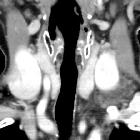

Subclavian

vein aneurysm - Case presentation and discussion. Neck and thoracic inlet CT with intravenous contrast media in coronal reconstruction, in which a saccular aneurysm of the upper edge of the left subclavian vein can be seen (arrow), without evidence of rupture.